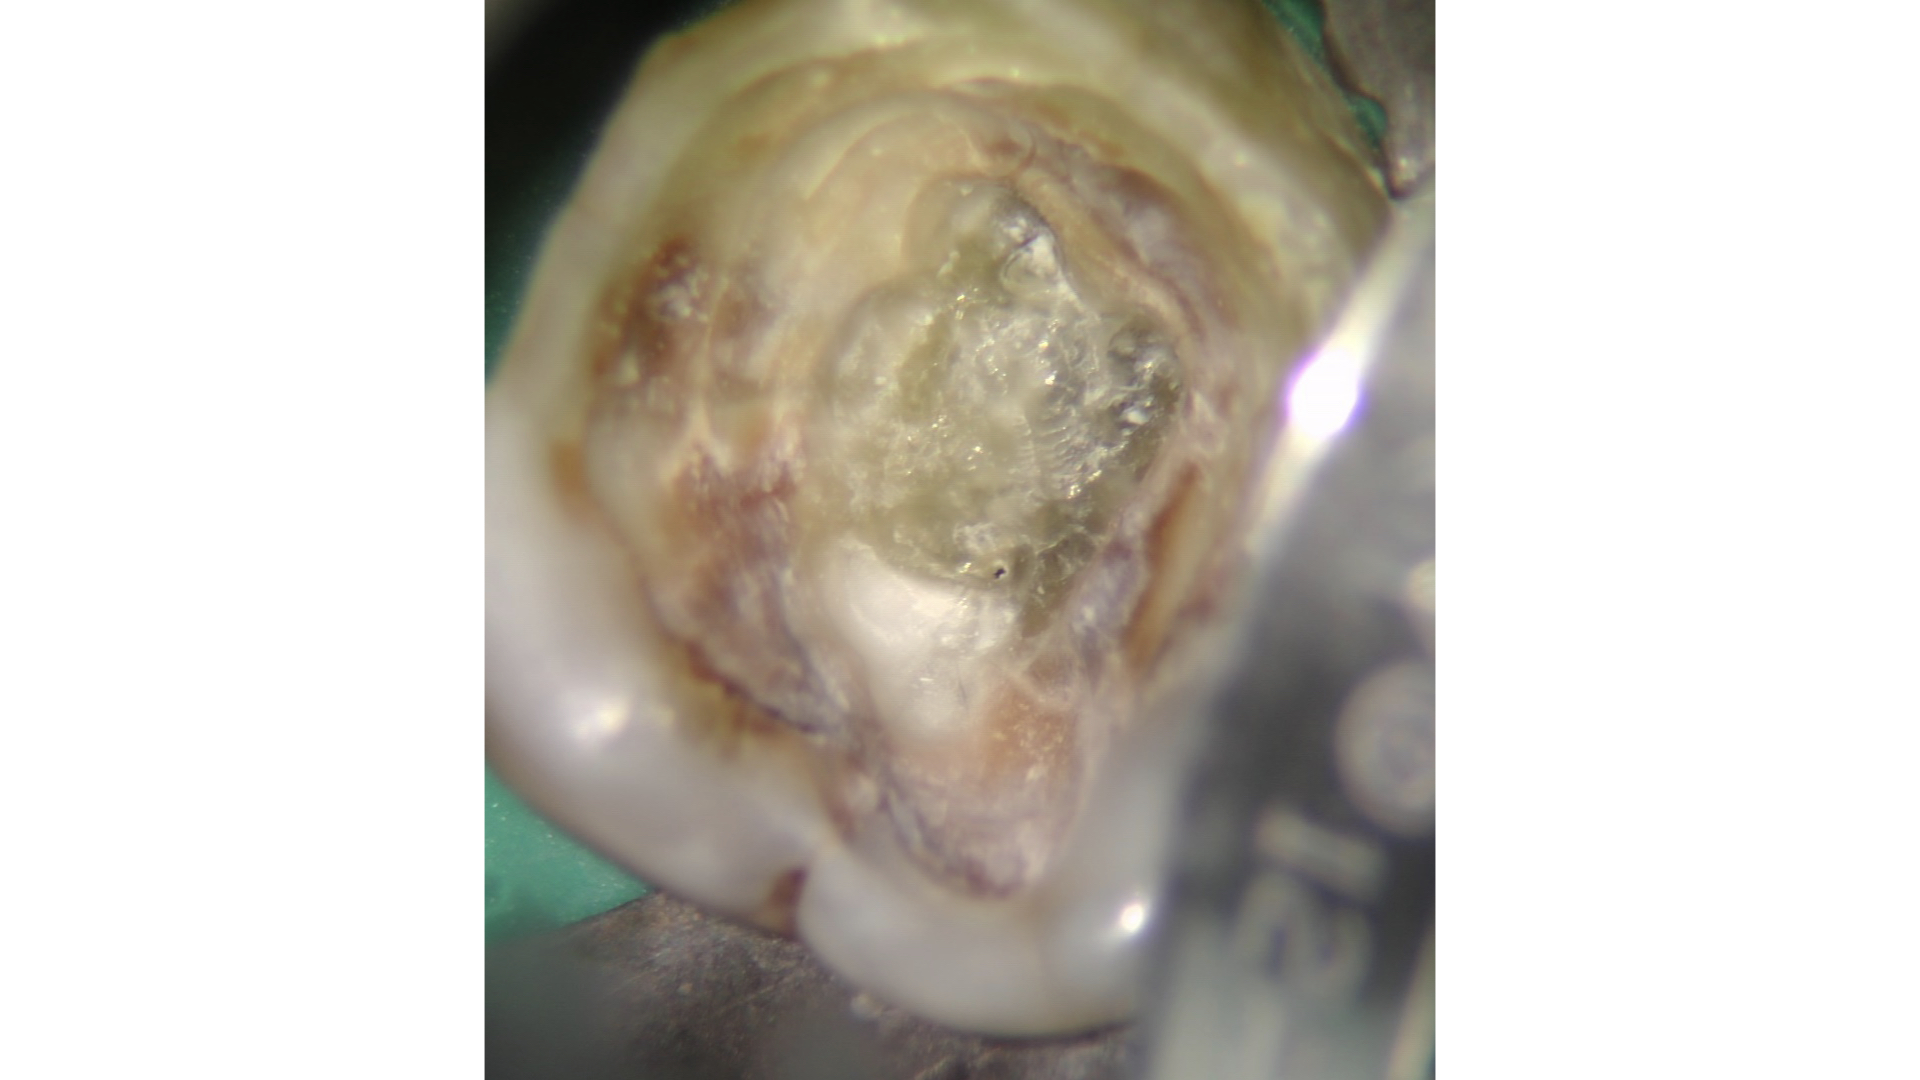

Il pavimento della camera pulpare si presenta sempre con un aspetto più scuro ed opaco rispetto al tessuto calcificato che tende ad essere lucido con un effetto che potremmo definire “vetrificato” (Figure 15-20).

Talvolta la differenza è evidente, in altri casi molto più sottile e quindi anche le difficoltà incontrate possono essere maggiori.